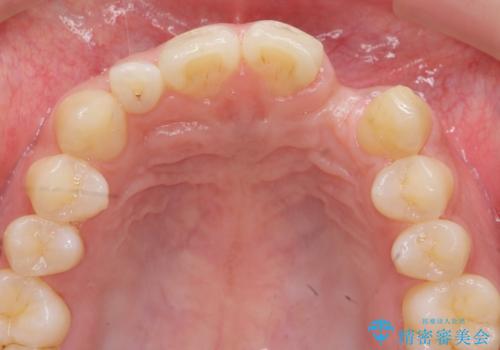

前歯部 インプラント治療

- 前歯の永久歯が元々なく、乳歯を失ったタイミングで前歯の審美性の回復を求めて来院されました。

機能・審美性の回復手段として、インプラント治療・ブリッジ・部分床義歯が考えられます。

それぞれの治療に特徴がありますが、取り外しの必要がなく隣の歯を削る必要も必要ないインプラント治療を選択されました。

前歯部にインプラントを埋入し、きれいに仕上げるためには骨の造成技術や歯肉の厚みを増すような処置を行い、インプラント周囲の環境を整備することが肝要です。